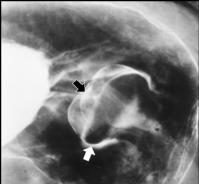

Image en

laculaire eleve intra luminale gastrique a

nultilobulaire ou epassisement de gros plis . S'il y

avait lesion ulceree en association c'est tres

difficile de diagnostic differentielle avec

anenocarcinoma de l'estoma .Image TOGD avec

compressive region antral . |

Meme cas en double de

contrast.TOGD .. |